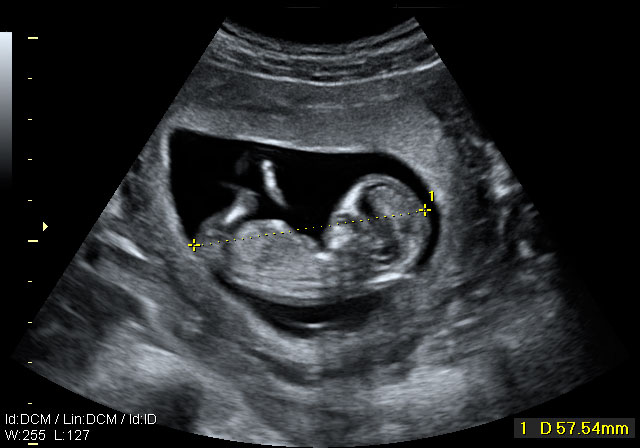

Ecografía semana 12: Cabeza, tronco y cordón umbilical

La cabeza aún es muy grande respecto al cuerpo

Se pueden apreciar con toda claridad la cabeza (aún más grande en proporción, que el resto del cuerpo), el tronco, las extremidades y el cordón umbilical. El niño ya se apoya con la espalda en el útero materno, lo que facilita la exploración por parte del ecografista.

Ecografía Embarazo 2D y 3D - SEMANA 12